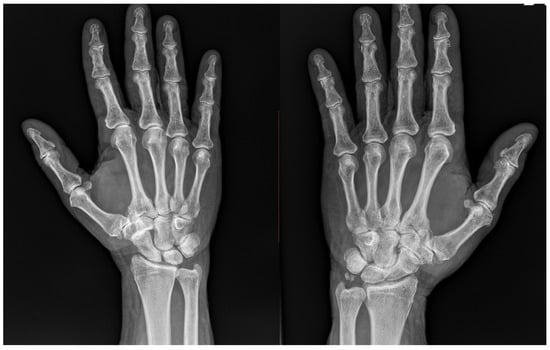

A 71-year-old male patient was referred to our clinic in May 2024 with a diagnosis of bilateral trapeziometacarpal osteoarthritis. His medical history included hypertension and paroxysmal atrial fibrillation, with no conditions affecting hand function or influencing surgical planning. Radiographic evaluation revealed grade 3 osteoarthritis of the right trapeziometacarpal joint according to the Eaton–Littler classification. Despite the degenerative changes, the trapezium maintained adequate bone stock, making the patient a suitable candidate for trapeziometacarpal prosthesis implantation.

Conversely, the left hand presented combined scaphotrapeziotrapezoidal (STT) and trapeziometacarpal arthritis. A slight reduction in trapezial bone stock was observed, but the primary indication for trapeziectomy was the presence of STT arthritis, which represented the predominant pathological finding and guided the choice of suspension arthroplasty.

Preoperative radiographs illustrating the bilateral TMC pathology are shown in Figure 1.

Figure 1. Preoperative radiographs showing bilateral trapeziometacarpal joint osteoarthritis: grade 3 degeneration with preserved trapezium on the right, and advanced scaphotrapezial–trapeziometacarpal arthritis with a slight reduction in trapezial bone height on the left.